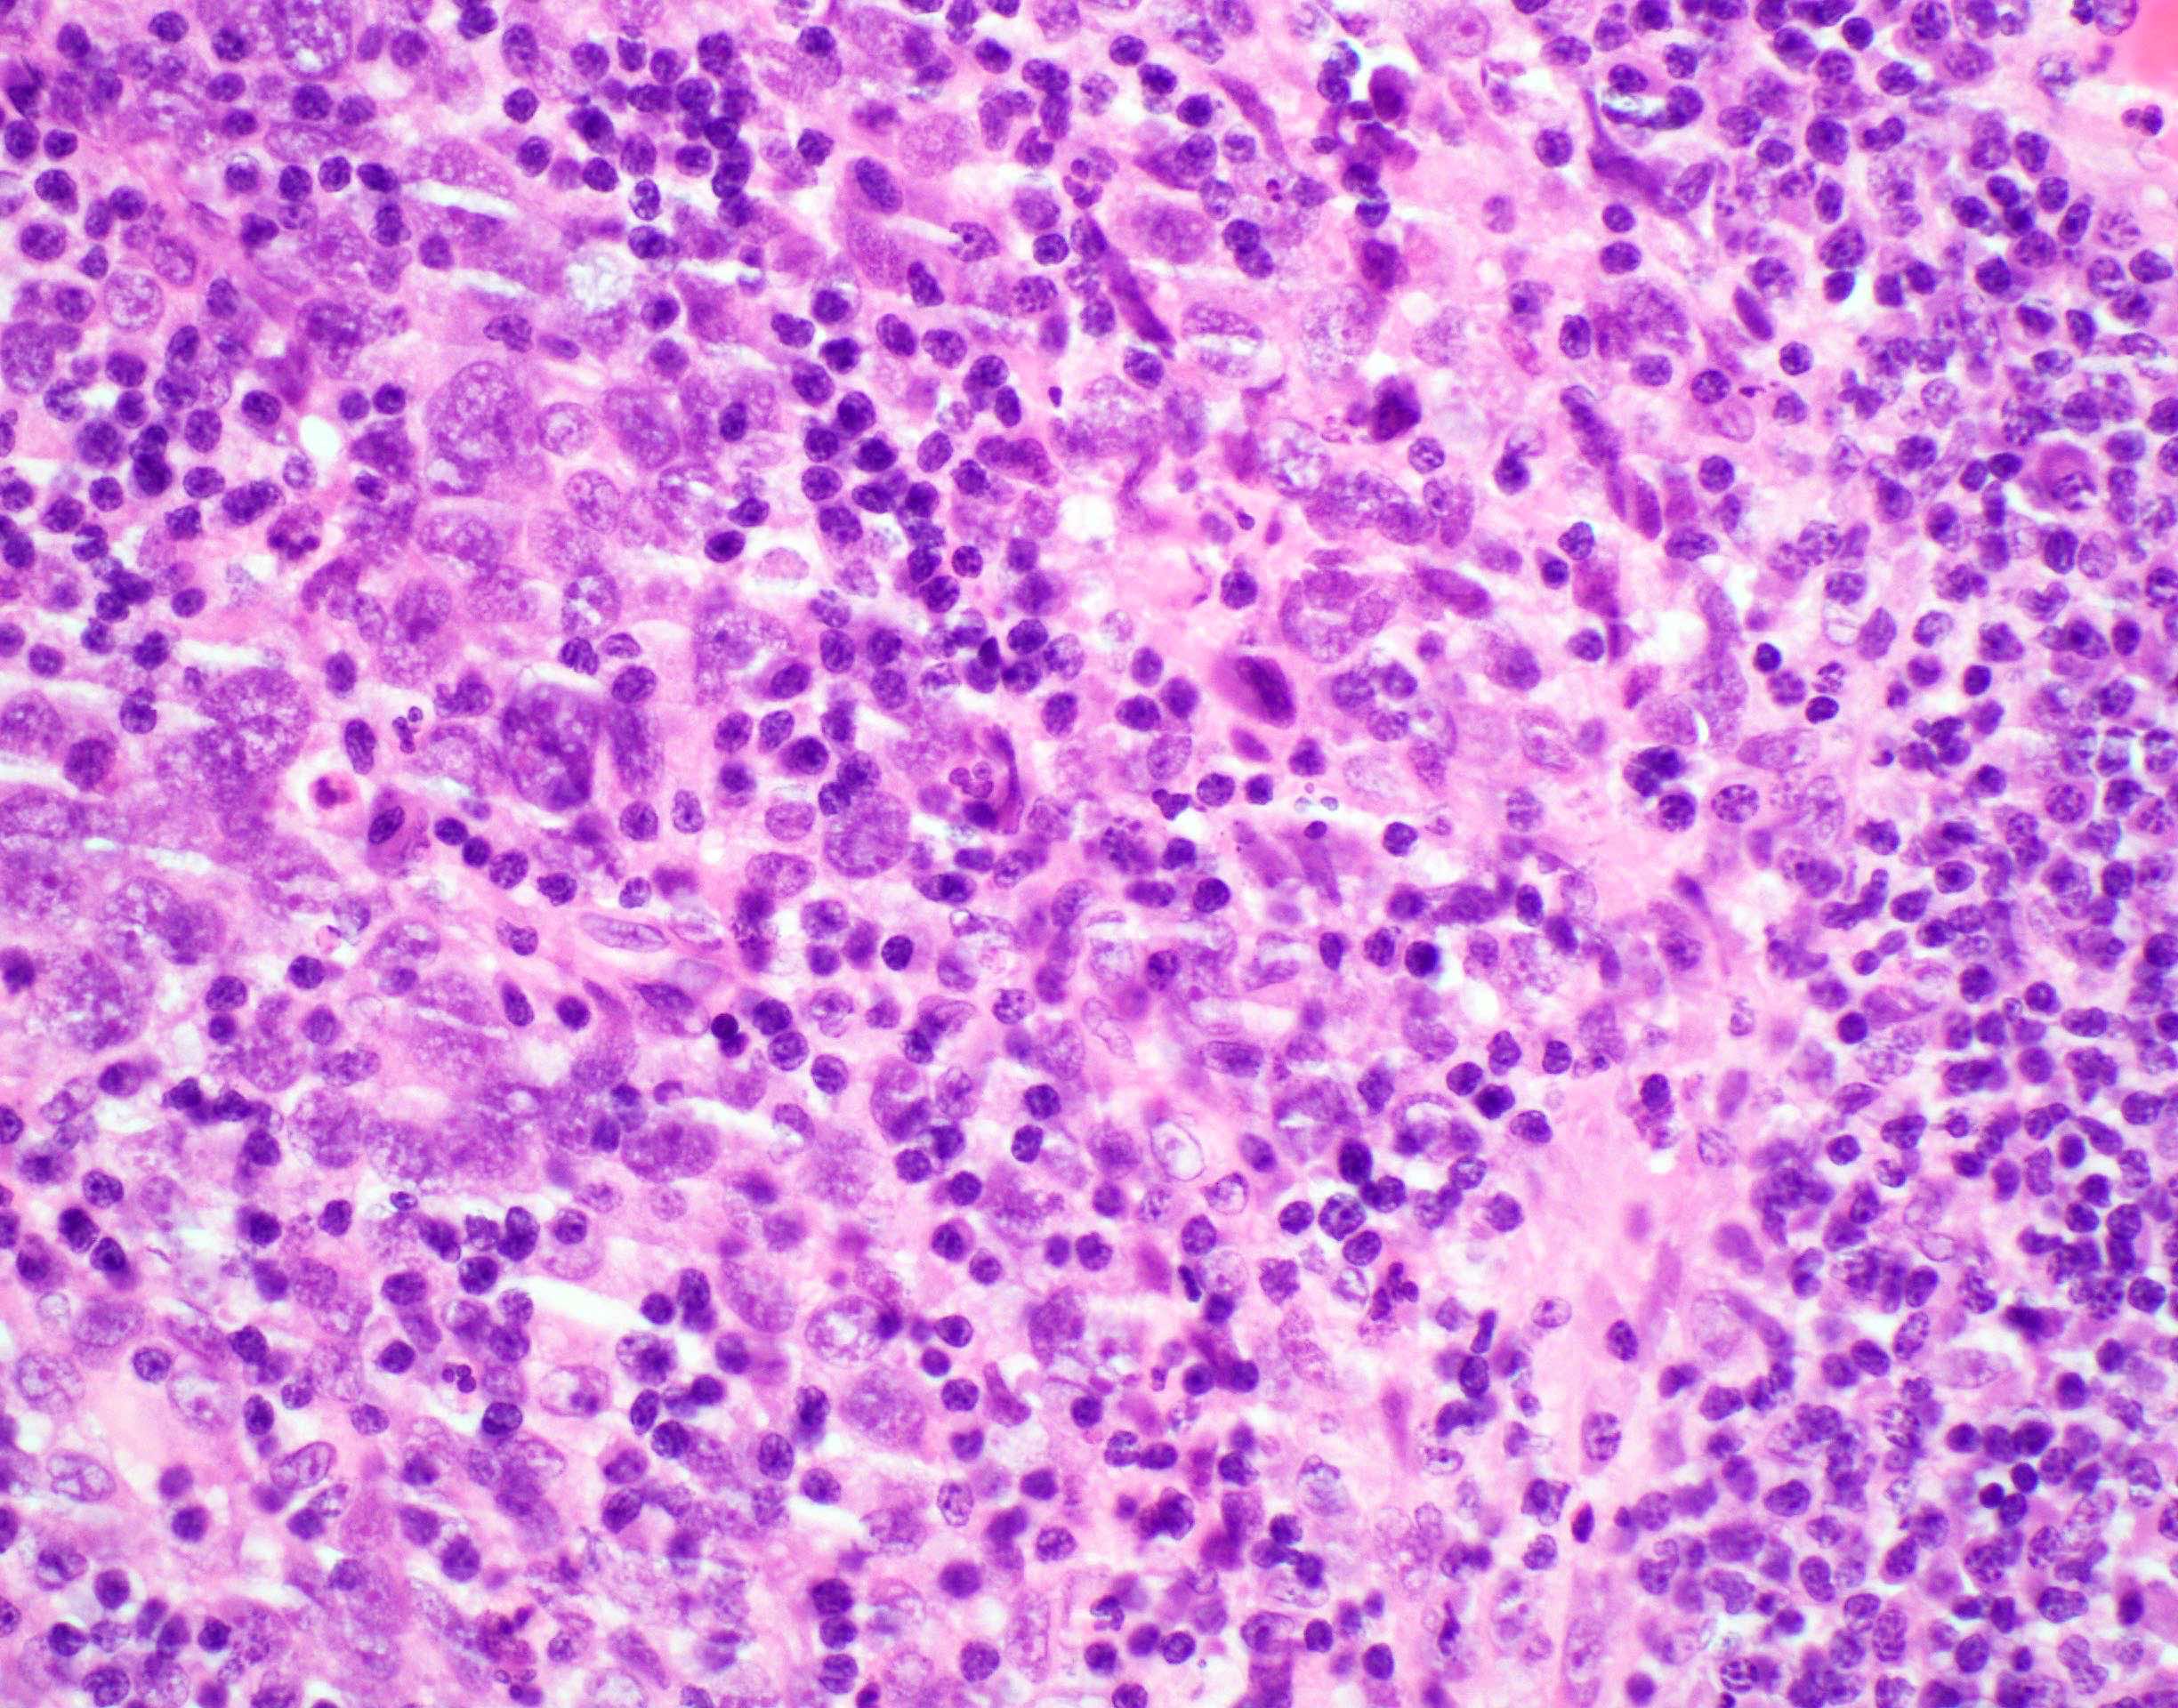

Microscopic (histologic) description

- Squamous cell carcinoma, conventional

- Most common and typical morphology of conventional keratinizing squamous cell carcinoma at any site

- Large polygonal malignant cells with intercellular bridges

- Cytoplasmic or extracellular eosinophilic keratin

- Dyskeratotic cells and squamous pearls

- Nuclear size, pleomorphism, hyperchromasia and mitoses increase with increasing grade

- Lymphoepithelial carcinoma (nonnasopharyngeal) (Head Neck Pathol 2011;5:327)

- Cohesive tumor nests of nonkeratinising epithelioid cells with prominent intermixed reactive lymphoplasmacytic infiltrate

Microscopic (histologic) images

Contributed by Ruta Gupta, M.B.B.S., M.D.